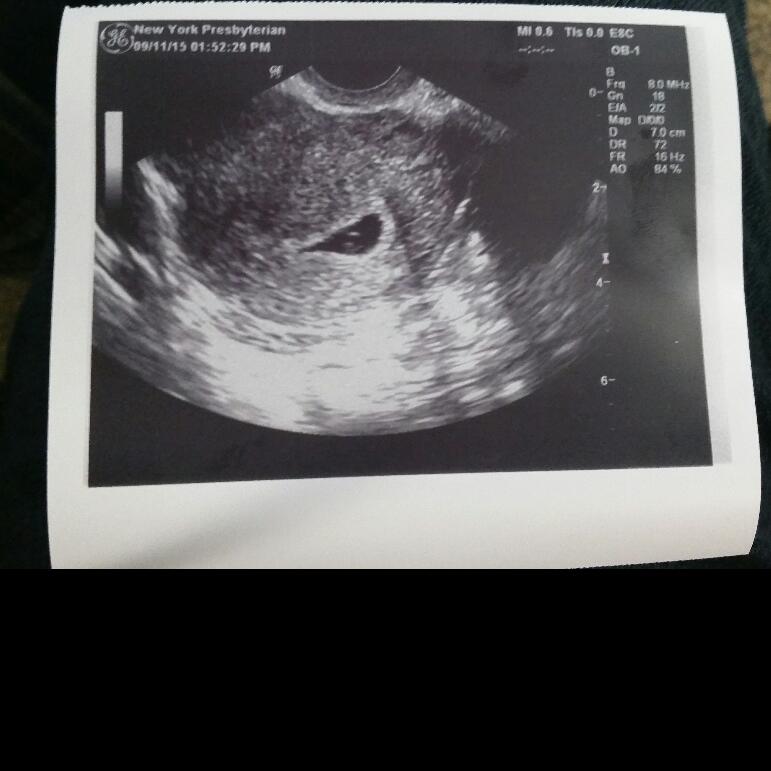

New discussion button is missing for me on my laptop. I had my first appt today expecting to be 8 weeks based on LMP. They did a transvaginal ultrasound because they were worried about a possible cyst and the sac was measuring at only 5w4d. You couldn't see anything in it yet. Based on when I think I ovulated, this would make sense... my cycles are usually long... but that didn't stop me from bursting into tears. Neither the tech or the doctor were worried and they want me to come back in 2 weeks for another ultrasound, but I'm freaking out. Is 5w4d just too early to see anything? Did anyone else have their EDD completely wrong when they went for an ultrasound?

If your cycles are unusually long, you shouldn't have based how far along you thought you'd be on your LMP. So, if you are only 5w4d, seeing the gestational sac sounds fine. I only saw the gestational sac at 5w2d, saw the yolk sac four days after that and saw the heartbeat at my 7w appointment. I know it's really hard (especially when so many other women see things a lot earlier), but try to remain calm and think positively.